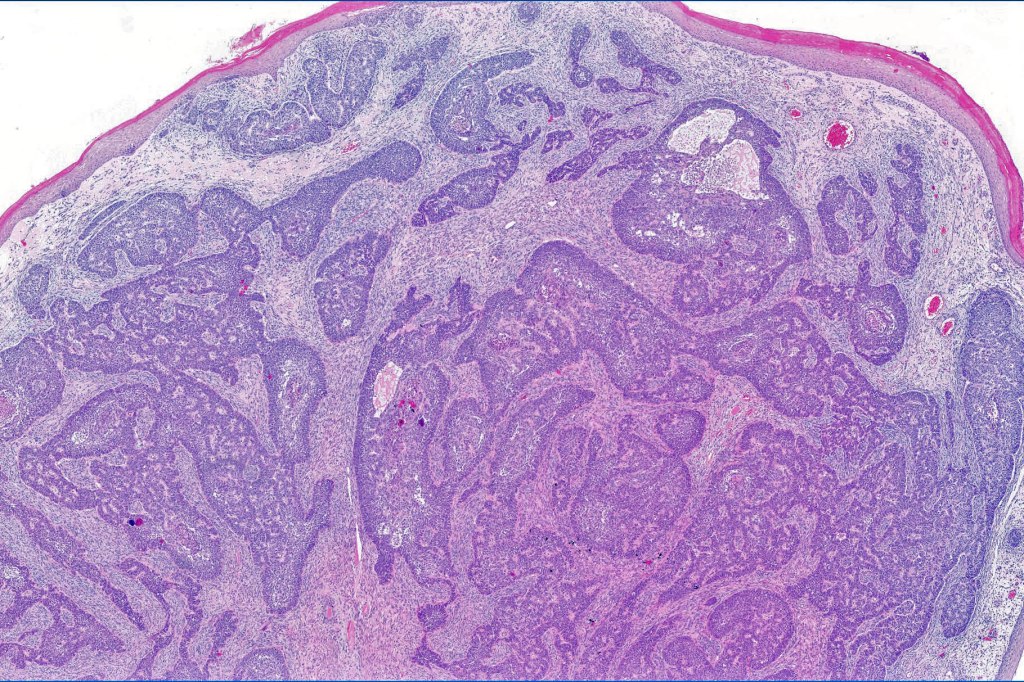

Histological features

•Low grade trichoblastic carcinoma is easily recognized as trichoblastomatous but shows an infiltrating margin with deep involvement into subcutaneous fat +/- muscle